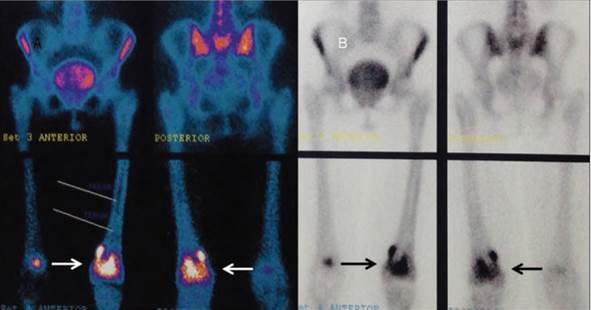

Mujer de 61 años de edad. Inició su padecimiento el 12 de septiembre del presente año con dolor en rodilla izquierda e imposibilidad para deambular. Acude con su médico, quien solicitó radiografías (Figura 6) en las que se observaron imágenes centrales líticas que afectan el tercio distal del fémur izquierdo con edema de partes blandas. Tomografía y gammagrama (Figura 7) que muestra en la fase de equilibrio una zona de hipercaptación con componente mixto de predominio lítico y que involucra la cortical. Se obtiene biopsia y se sospecha diagnóstico de plasmocitoma, motivo por el cual acude a consulta de hematología.

Figura 7 Gamagrama óseo con zona central de hipercaptación focalizada en el tercio distal del fémur izquierdo que involucra la cortical (flechas).

Se obtuvo aspirado de médula ósea que confirmó el diagnóstico de MM con > 20% de células plasmáticas anormales. Inmunoglobulina G (IgG) con riesgo pronóstico bajo (beta-2-microglobulina 3.5 y albúmina normal). Se inicia con ácido zoledrónico, talidomida (100 mg/día) y dexametasona (40 mg a la semana por 4 semanas y descansa 1 semana). Logró mejoría de la sintomatología, sin dolor o limitación de la marcha.

En septiembre se obtuvieron nuevas placas de rodilla, ahora con mínimas lesiones, y se decidió tomar nueva RM (Figura 8) que mostró tumor del espacio que afecta la porción central de la médula ósea, del tercio distal de contornos irregulares, espiculados con intensidad de señal heterogénea en todas las secuencias y mostró realce periférico con la aplicación de gadolinio, hipointenso en T1 e hiperintensa en T2, con afectación de la cortical por la toma de la biopsia. En octubre se ajustó el tratamiento con talidomida durante 7 días 2 veces al mes y continúa igual con dexametasona; Se indicó radioterapia a rodilla izquierda para tratar enfermedad residual.